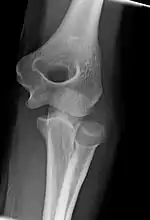

Left elbow extended and flexed

Left elbow-joint

Left: anterior and ulnar collateral ligaments

Right: posterior and radial collateral ligaments

Normal radiograph; right picture of the straightened arm shows the carrying angle of the elbow

Left: Lateral X ray of a dislocated right elbow

Right: AP X ray of a dislocated right elbow